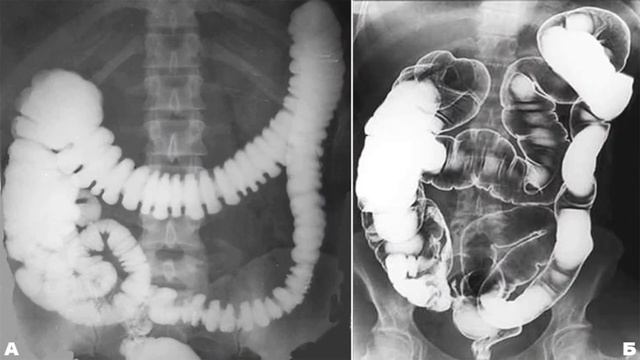

Иллюстрации и информация о симптомах острого кишечного непроходимости